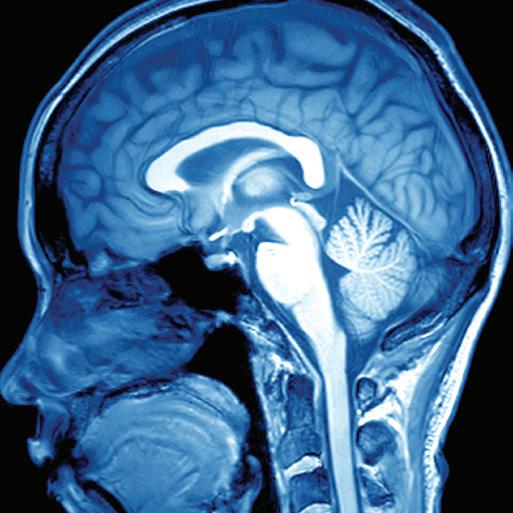

THESE RESULTS FROM THE PROSPECTIVE, multicentre, randomised HOPE study offer promise to stroke patients worldwide who may not be able to access clot-dissolving medications within the approved time window—which, in China, is within 4.5 hours—according to the trial’s principal investigator Min Lou (Second Affiliated Hospital of Zhejiang University School of Medicine, Hangzhou, China).

in hospitals that use CT [computed tomography] perfusion imaging. This technology helps healthcare professionals see how blood flows in different parts of the brain after an ischaemic stroke. This could extend treatment eligibility to millions more patients across the globe.”